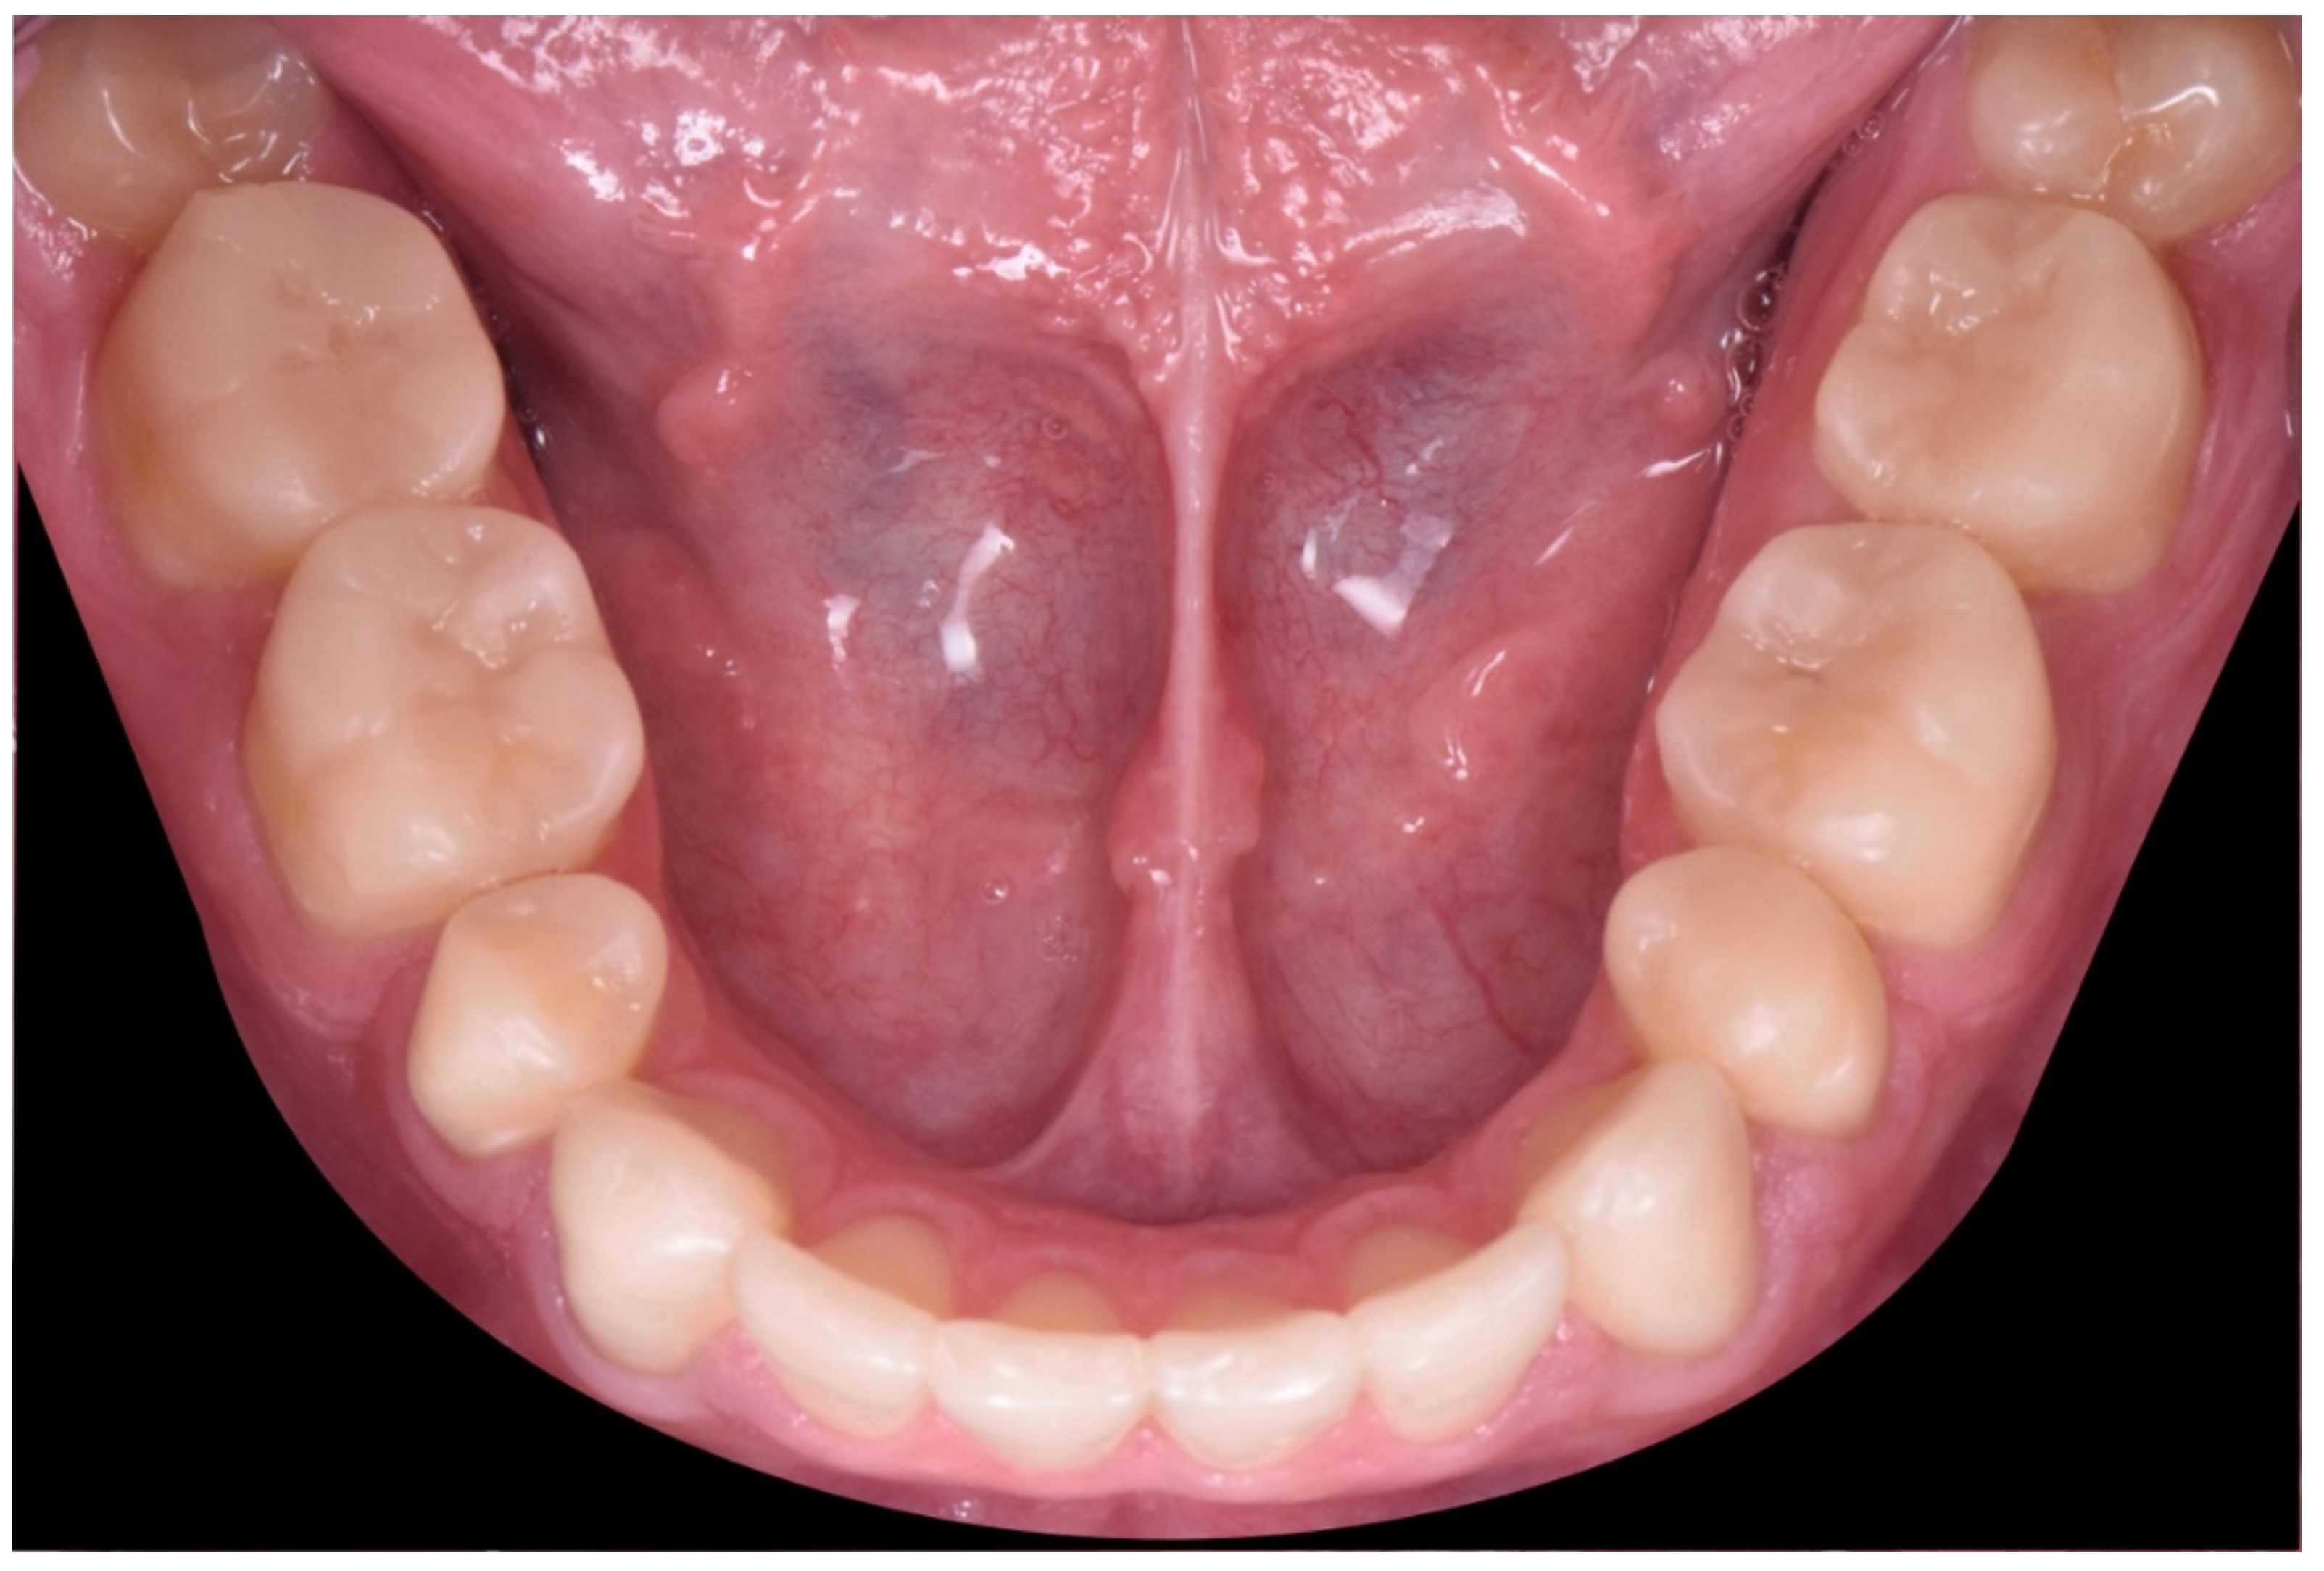

2. Clinical Report

2.1. Planning Phase